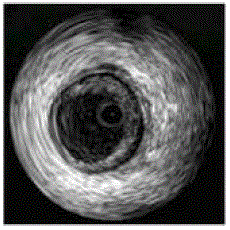

Analise a imagem ultrassonográfica intracoronariana abaixo e assinale a assertiva correta.